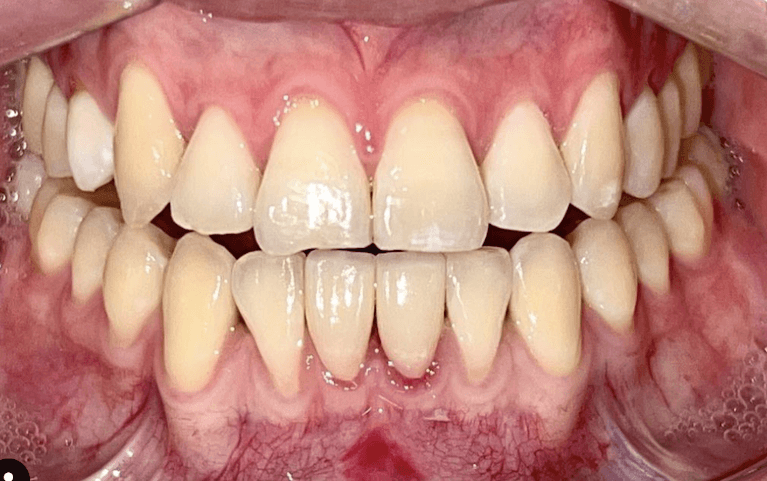

Before and after with Invisalign orthodontic treatment. Pictures taken with different phones at different setting. Used total of 27 aligners/trays. Treatment time 13.5 months